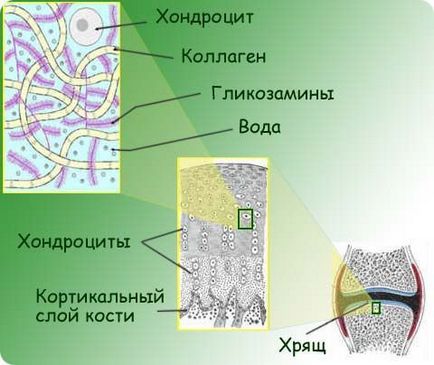

Ce este cartilaj

cartilajului articular în articulația genunchiului joacă un rol foarte important pentru mișcarea umană. Este un elastic puternic căptușeală,, netede, principalele funcții din care sunt:

- de distribuție a sarcinii în timpul de mers pe jos;

- Furnizarea de os ușor să alunece în raport cu celălalt.

Sânge în genunchi este aproape nu ajunge (fără capilare în cartilajului articular). În lipsa alimentației și creșterea țesutului repararea cartilajului corespunzătoare sunt imposibile. Pentru a sprijini cartilaj existență a forțat-o să ia vitamine și minerale necesare din lichidul sinovial.

Pentru regenerarea cartilajului țesut are loc rapid, este necesar să se mențină un nivel ridicat de condrocite - celule de bază ale cartilajului țesut. Acest lucru se realizează prin nutriție adecvată, ceea ce este posibil prin intermediul lichidului sinovial. Cu toate acestea, în cazul în care articulația genunchiului va rămâne staționară, nutrienți nu pot penetra tesatura. Restabilirea cartilajului articular este aproape complet dependentă de activitatea motorie.